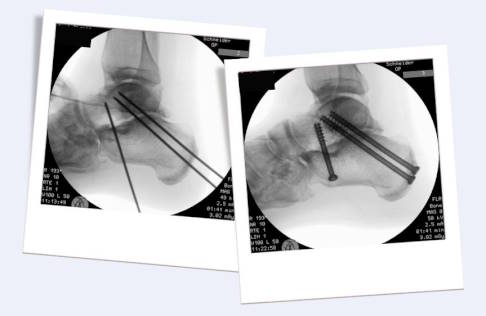

Nach der Korrektur werden die Knochen meist mit Schrauben oder alternativ mit Plattensystemen stabilisiert und fixiert. Im Rahmen einer Schraubenosteosynthese bringt der Operateur zunächst unter Röntgen oder arthroskopischer Sicht Drähte ein. Nach korrekter Lage dieser Drähte werden Löcher gebohrt und Schrauben über den noch vorhandenen Gelenkspalt eingedreht. Die Schrauben sorgen dafür, dass die Knochen korrekt stabilisiert sind und komprimiert werden. Auf diese Weise wachsen Sprungbein und Fersenbein im Bereich des ehemaligen Subtalargelenks zusammen.

Subtalare Arthrodese in der Durchleuchtung: Links nach Einführen der Führungsdrähte, rechts die finale Fixierung mit Schrauben. © Gelenk-Klinik